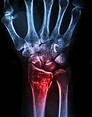

Existing complex fracture treatments heavily rely on rigid metal fixators such as screws, generalised plates and pins. In response, the clinical community has raised key concerns and demonstrated a growing demand for customisation, driving the search for alternative solutions that enable truly personalised fixation surgical treatments. ​Through innovating our Bonevolent™ technology, BMB provides a platform empowering surgeons to provide an alternative of customisable care. ​

AdhFix is an implant which adapts to any bone shape and possesses high load-bearing properties. It leverages mechanical fixators and eliminates use of metal plates. With excellent compatibility to soft tissue, we minimise adverse effects associated with standard-of-care metal plates. ​

Its high degree of customisability allows it to serve as a universal solution, with particular effectiveness in managing complex, comminuted fractures.

Our recommended indications for AdhFix include: ​

Hand, distal radius, ankle, maxillofacial & cranial.